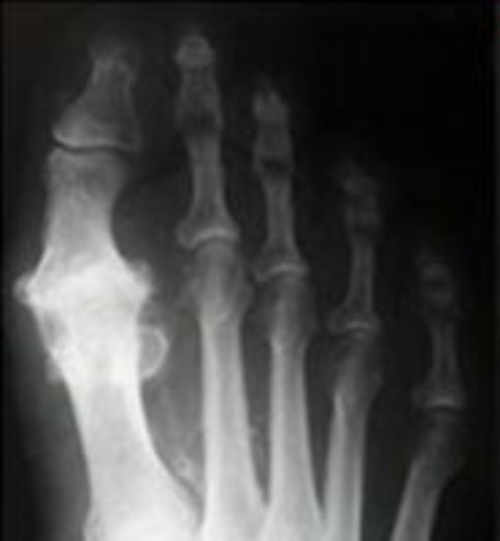

El diagnóstico del Hallux Rigidux se confirma con una exploración clínica junto con radiografías que evidencian una degeneración articular y proceso artrósico con presencia de osteofitos (crecimiento de hueso) en la base de la falange y cabeza del primer metatarsiano con anquilosis de la articulación.

El Hallux Rigidus es una patología de la primera articulación metatarsofalángica que produce una pérdida progresiva de la movilidad del primer dedo del pie.

Cuando esta patología evoluciona y se va estructurando perdiendo totalmente la movilidad tanto en dinámica como en reposo, hablaremos de “Hallux Rigidus”. Según va avanzando el proceso degenerativo flexionar el dedo se vuelve más y más difícil.

Los síntomas y signos del Hallux Rigidux son varios, pero los más comunes son la presencia de dolor y rigidez en el primer dedo al caminar, presentando un bloqueo de la articulación en la fase de despegue. Esto conlleva a múltiples micro traumatismos que aceleran el proceso degenerativo de la articulación.